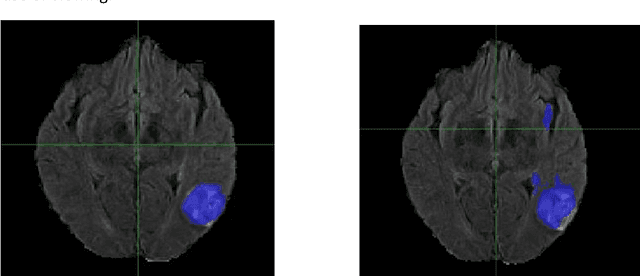

Abstract:Although machine learning (ML) has shown promise in numerous domains, there are concerns about generalizability to out-of-sample data. This is currently addressed by centrally sharing ample, and importantly diverse, data from multiple sites. However, such centralization is challenging to scale (or even not feasible) due to various limitations. Federated ML (FL) provides an alternative to train accurate and generalizable ML models, by only sharing numerical model updates. Here we present findings from the largest FL study to-date, involving data from 71 healthcare institutions across 6 continents, to generate an automatic tumor boundary detector for the rare disease of glioblastoma, utilizing the largest dataset of such patients ever used in the literature (25,256 MRI scans from 6,314 patients). We demonstrate a 33% improvement over a publicly trained model to delineate the surgically targetable tumor, and 23% improvement over the tumor's entire extent. We anticipate our study to: 1) enable more studies in healthcare informed by large and diverse data, ensuring meaningful results for rare diseases and underrepresented populations, 2) facilitate further quantitative analyses for glioblastoma via performance optimization of our consensus model for eventual public release, and 3) demonstrate the effectiveness of FL at such scale and task complexity as a paradigm shift for multi-site collaborations, alleviating the need for data sharing.

Abstract:Every year thousands of patients are diagnosed with a glioma, a type of malignant brain tumor. Physicians use MR images as a key tool in the diagnosis and treatment of these patients. Neural networks show great potential to aid physicians in the medical image analysis. This study investigates the use of varying amounts of synthetic brain T1-weighted (T1), post-contrast T1-weighted (T1Gd), T2-weighted (T2), and T2 Fluid Attenuated Inversion Recovery (FLAIR) MR images created by a generative adversarial network to overcome the lack of annotated medical image data in training separate 2D U-Nets to segment enhancing tumor, peritumoral edema, and necrosis (non-enhancing tumor core) regions on gliomas. These synthetic MR images were assessed quantitively (SSIM=0.79) and qualitatively by a physician who found that the synthetic images seem stronger for delineation of structural boundaries but struggle more when gradient is significant, (e.g. edema signal in T2 modalities). Multiple 2D U-Nets were trained with original BraTS data and differing subsets of a quarter, half, three-quarters, and all synthetic MR images. There was not an obvious correlation between the improvement of values of the metrics in separate validation dataset for each structure and amount of synthetic data added, there is a strong correlation between the amount of synthetic data added and the number of best overall validation metrics. In summary, this study showed ability to generate high quality synthetic Flair, T2, T1, and T1CE MR images using the GAN. Using the synthetic MR images showed encouraging results to improve the U-Net segmentation performance which has the potential to address the scarcity of readily available medical images.